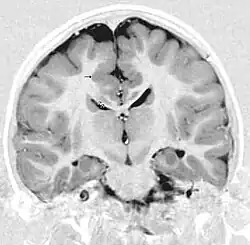

Gray matter heterotopia

MRI of a child experiencing seizures. There are small foci of grey matter heterotopia in the corpus callosum, deep to the dysplastic cortex. (double arrows)

Gray matter heterotopia is a neurological disorder caused by gray matter being located in an atypical location in the brain.[1]

Grey matter heterotopia is characterized as a type of focal cortical dysplasia. The neurons in heterotopia are otherwise healthy; nuclear studies have shown glucose metabolism equal to that of normally positioned gray matter.[2] The condition causes a variety of symptoms, but usually includes some degree of epilepsy or recurring seizures, and often affects the brain's ability to function.